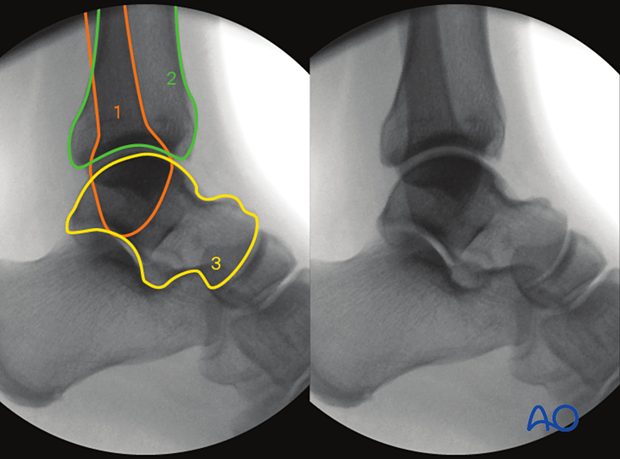

Рис. 2. Варианты строения межберцового синдесмоза

Рис. 3. Суставная поверхность межберцового синдесмоза

Межберцовый синдесмоз образован двумя костями и четырьмя связками. Медиальная шероховатая выпуклая поверхность дистального отдела малоберцовой кости сочленяется с латеральной треугольной малоберцовой вырезкой дистального отдела большеберцовой кости (incisura tibialis), формируя фиброзное соединение.

Размер и форма вырезки большеберцовой кости играют важную роль в патологии голеностопного сустава. Мелкая вырезка может предрасполагать к рецидивирующим растяжениям или повреждениям синдесмоза с переломо-вывихами. Передний бугорок большеберцовой кости (бугорок Шапута, Chaput’s tubercle) крупнее заднего и препятствует смещению малоберцовой кости кпереди. Более скромный задний бугорок допускает смещение малоберцовой кости кзади. При переломах малоберцовой кости, вызванных наружной ротацией, задний бугорок выступает точкой опоры (fulcrum), вокруг которой дистальный отдел малоберцовой кости ротируется кнаружи вдоль своей продольной оси.

Малоберцовая часть синдесмоза конгруэнтна большеберцовой. Межкостный гребень малоберцовой кости (crista interossea fibularis) образует выпуклый треугольник, расположенный проксимальнее суставной фасетки наружной лодыжки. Основание этого треугольника сформировано передним бугорком (бугорок Вагстафа — Ле Фора, Wagstaffe–Le Fort tubercle) и практически незаметным задним бугорком.

Рис. 4. Тибиофибулярная контактная зона (вид снизу, кадаверный препарат). 1 — хрящевая часть (истинный синовиальный сустав, высота 4 мм, длина 8 мм); 2 — центральная часть с V-образной синовиальной складкой. Стрелка указывает на верхнюю границу (уровень межкостной связки). Границы контактной зоны: БММС сверху, ПНБМс спереди, ЗНБМС сзади.